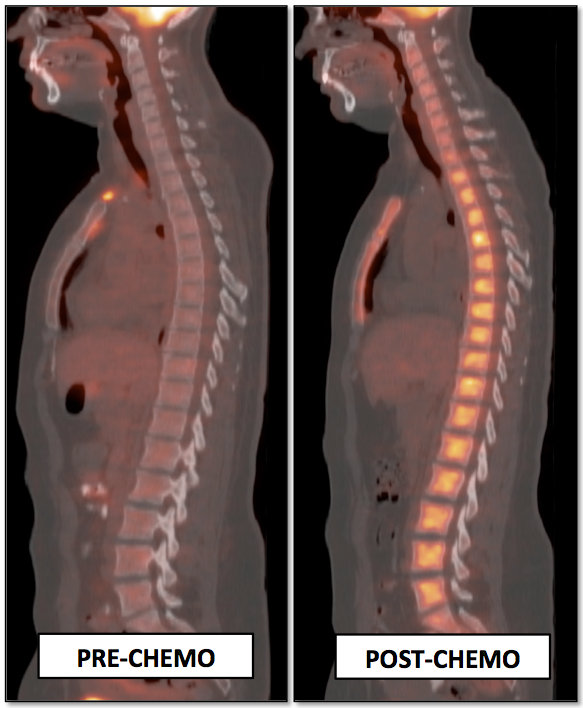

- Assess Response to Therapy

3. Timing of PET/CT Exam After Therapy

- “Rule of 3”

- Chemotherapy: 1 month